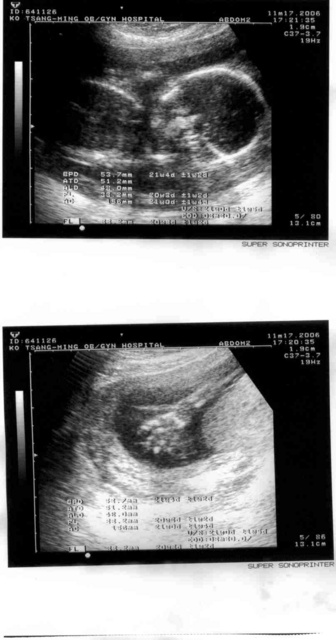

2006.11.17

終於是換了一家醫院,換到柯滄銘,離家遠一點,離公司近一點,五點半就停止掛號,要陪老婆去產撿就辛苦一點了,However,我們還是想要圖個安心。

這家老醫生的醫術醫德看來都讓人放心,設備稍微老舊,從超音波的解析度就可以看的出來。小朋友堅持背對鏡頭,所以依然沒有看到他的輪廓,不過看到小朋友的手掌像是在跟我們說嗨,感覺很是可愛。